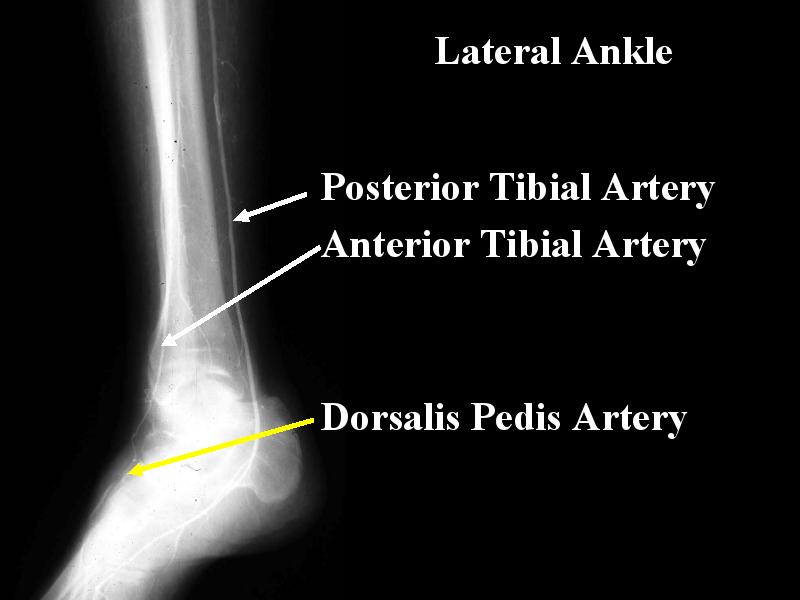

MS 112 RUNOFF LAT ANKLE